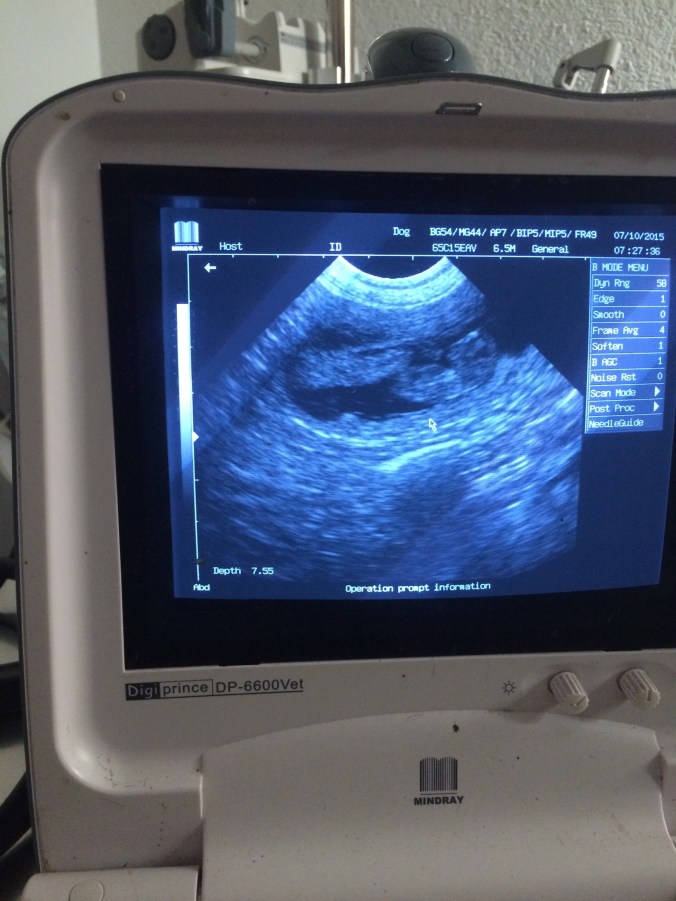

30 dagar har gått sedan parning och hon har gått upp 1 kg. Åkte in för att ultraljuda henne imorse för att se om där var några valpar. Men med de tecken jag har sett de senaste veckorna rådde det inga tvivel om att magen var full.

Vi fick se tre valpar på samma bild, det var en extremt häftig känsla. Fick även en bild på en valp med tassarna i luften.

Så nu är min magkänsla bekräftad. Valpar har hon. Sen hur många, det återstår att se. Med tanke på att de låg tätt så är där nog några stycken.